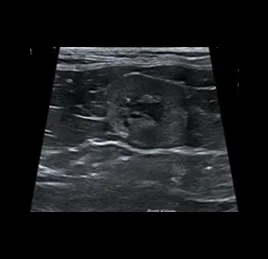

📍초음파 진단 케이스

• 지방간

• 담낭 점액종

• 비장 종양

• 수신증

• 만성 신부전

• 방광 결석

• 부신 종양

• 혈관 이상 - PSS

• 췌장염

• 췌장 농양

• 위장관염

• 소장 종양